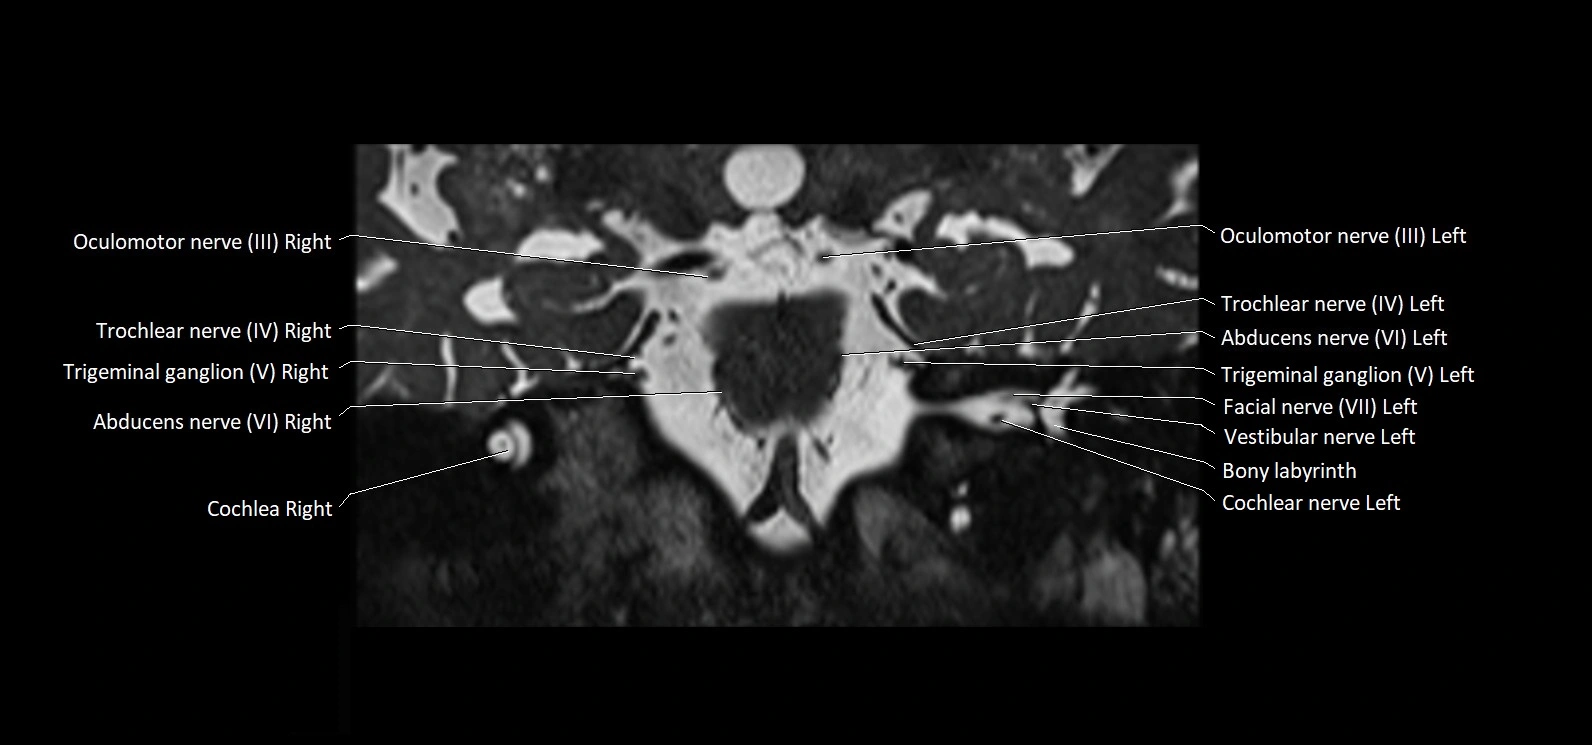

MRI Appearance

• The abducens nerve is a small, thin, linear structure

• Best visualized on high-resolution T2-weighted 3D MRI sequences (e.g., FIESTA or CISS)

• Seen as a hypointense (dark) line running from the brainstem at the pontomedullary junction, traversing the prepontine cistern, and entering Dorello’s canal under the petrosphenoidal ligament, then into the cavernous sinus, and finally the orbit

• May be challenging to visualize in standard MRI due to its small size

• Pathology may be inferred by absence, displacement, or enhancement of the nerve

MRI images

image